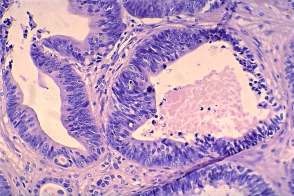

Histopathology: metastasis of a colon cancer to the thyroid.

• The less obvious failure was my cytological diagnosis. Knowing the final diagnosis, of course, I would say otherwise. And re-examining the cytology sample later helped to avoid a similar mistake. Although the cytological picture resembles that seen in papillary cancer, the cytological pattern should raise colonic cancer. The clue is the palisading arrangement of tumor cells.